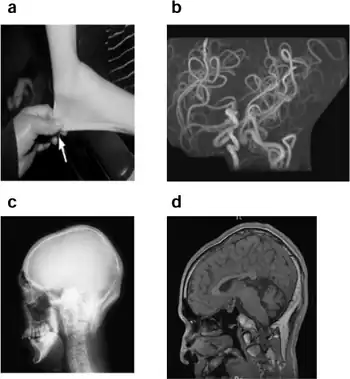

It is characterized by a deficiency in biliary copper excretion that causes deformations in the skeleton. These include projections on the back of the skull (parasagittal bone exostoses arising from the occipital bone—the so-called "occipital horns") as well as deformities of the elbow, radial head dislocation, hammer-shaped lateral ends of the clavicles, and abnormalities of the hips and pelvis.[1] OHS presents in early to middle childhood.[4] Children may present with features such as:

The initial diagnosis of Menkes disease (MD) and its milder variants such as Occipital Horn Syndrome is based on the clinical symptoms. Low serum copper and ceruloplasmin levels support the clinical suspicion of OHS, but biochemical confirmation in tissue culture is needed. The ultimate diagnostic proof is the demonstration of a molecular defect in ATP7A. Demonstration of the bony protuberances on the occiput will clinch the diagnosis, and these can be palpated in some patients.[9]